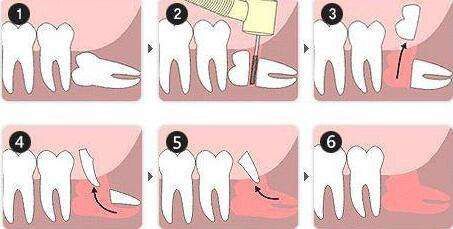

△微創拔牙——準确分割牙體并取出,告别傳統暴力拔牙方式。

張主任講,微創拔智牙融合了多種先進的技術和理念,讓拔牙方式徹底告别盲目、暴力時代,具有這些優勢:1、個性化。術前通過CBCT明确患牙形态、埋伏深度及與下槽骨神經管、鄰牙的關系,分析骨阻力,設計、制定個性化的方案。2、創傷小。根據患牙特征,以減小創傷爲目的設計切口,采用超聲刀、切牙機等先進儀器設備,以小切口暴露牙冠,對患牙進行準确分割後經小切口逐一取出,告别傳統敲、鑿、劈、撬等一系列機械性操作,大幅度減少對正常組織的損傷。3、疼痛小、并發症少、恢複快。微創技術的應用,大幅減少智牙拔除的疼痛以及并發症,加快了術後的恢複。